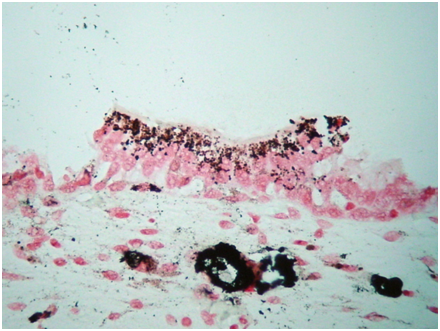

Clinical examination and radiological investigations including and ultrasound scan and a computerised axial tomogram scan (with intravenous contrast) of his urinary system were unremarkable. Routine blood tests including full blood count, urea, electrolytes and prostate specific antigen were normal. Urinalysis had revealed microscopic haematuria. There was no evidence of infection on urinalysis, mid-stream urine microscopy and culture. Urine cytology x 3 were normal. Flexible cystoscopy revealed several small, evenly pigmented, flat, brown/black lesions, measuring between 3 and 5mm in diameter, scattered throughout the bladder mucosa, with the greatest density and size of the lesions at the bladder base (Figure 1). Cold cup and subsequent resection biopsies were undertaken. There was no suggestion that the prostate could have been the source of his haematuria. Histopathology of both specimens showed many granules of golden brown pigment of varying size in the urothelial cells and within histiocytes in the underlying lamina propria (Figures 2&3).

No melanocytes were visible on routine staining with haematoxylin and eosin or with the immunoperoxidase stain S100 or with electron microscopy. The urothelium was not dysplastic. Some areas had metaplastic changes of cystitis cystica. The pigment was negative with Perl’s and with periodic acid Schiff (PAS) stains, excluding haemosiderin and lipofuscin respectively. Masson stain was positive, and bleaching removed the pigment, together indicating that the pigment was melanin. Electron microscopy showed that the pigment was bound in lysosomes and that there were no melanosomes (Figure 4). The final histopathological diagnosis was melanosis of the urinary bladder.